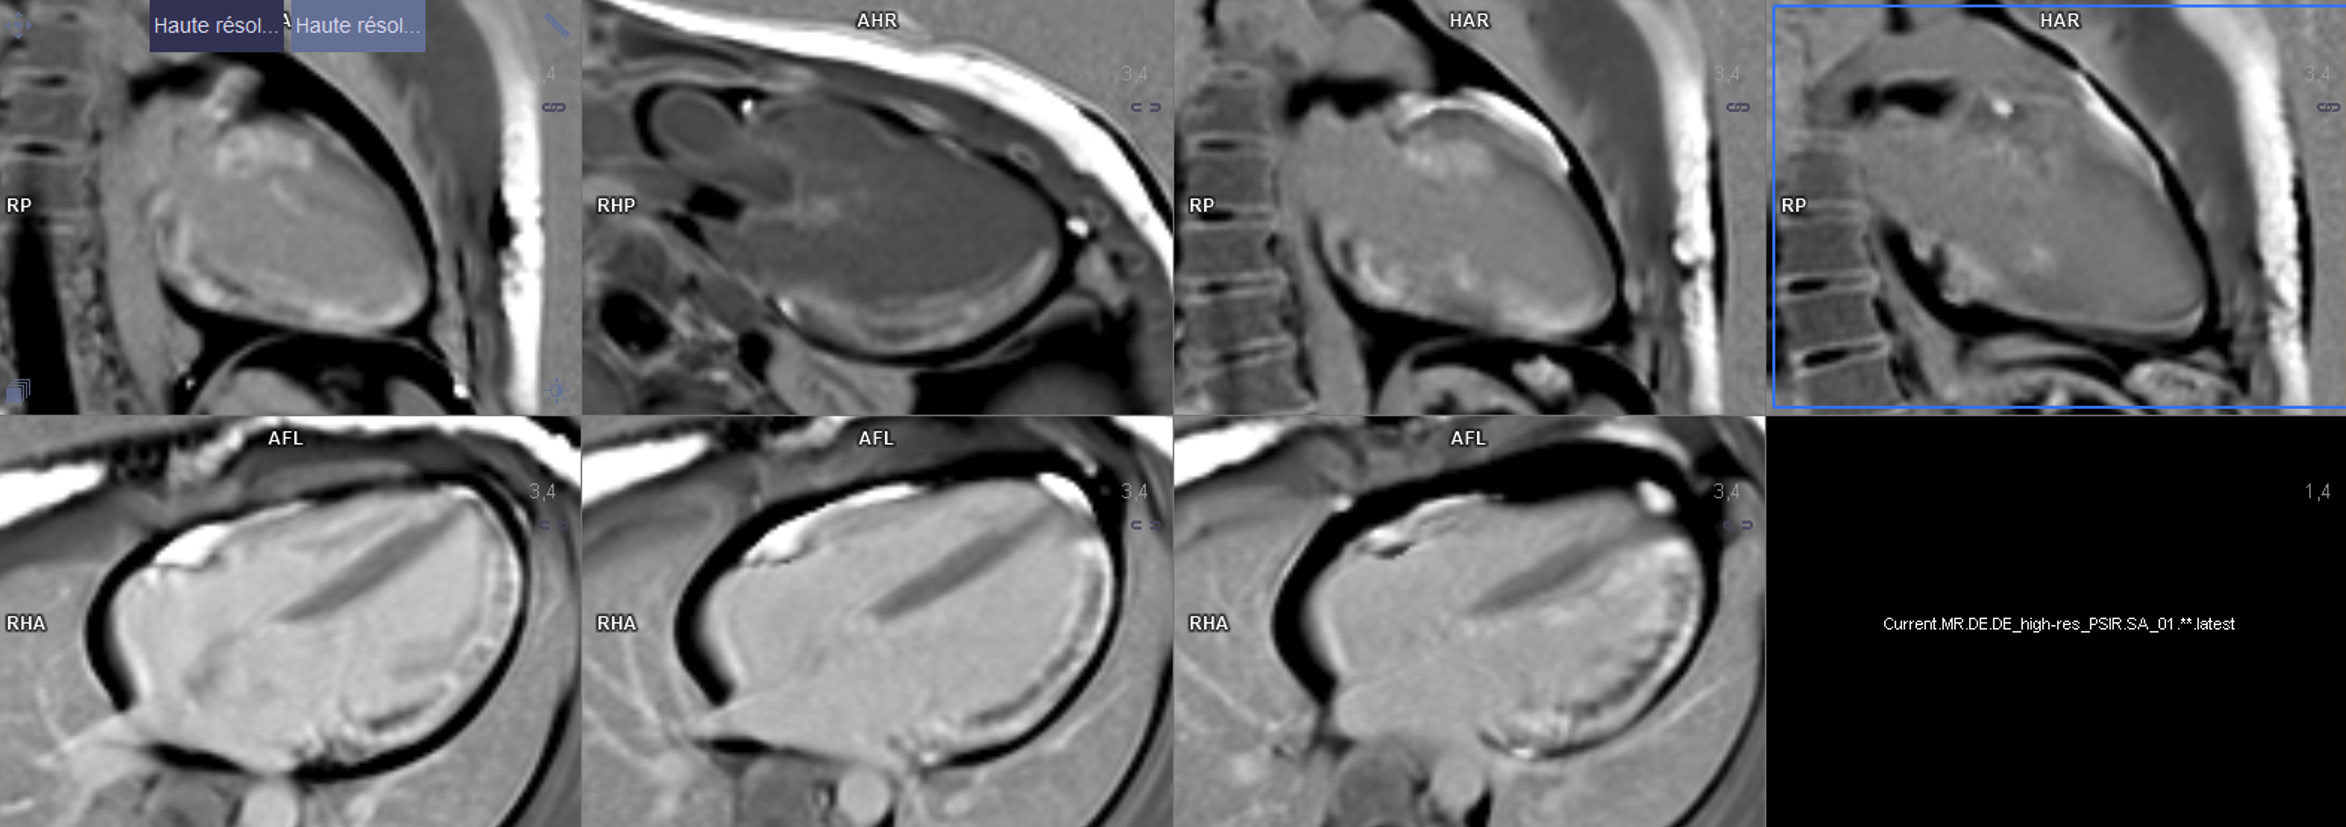

En raison d'une altération de la FEVG constatée dans les suites en ETT, une IRM myocardique objective une FEVG à 38 % et la présence d'une séquelle de nécrose transmurale sur 7 à 8 segments du territoire latéral débordant en antérieur et inférieur.

Une IRM myocardique de contrôle a été réalisée à 3 mois et objective une amélioration de la FEVG à 47 % malgré les séquelles transmurales persistantes.